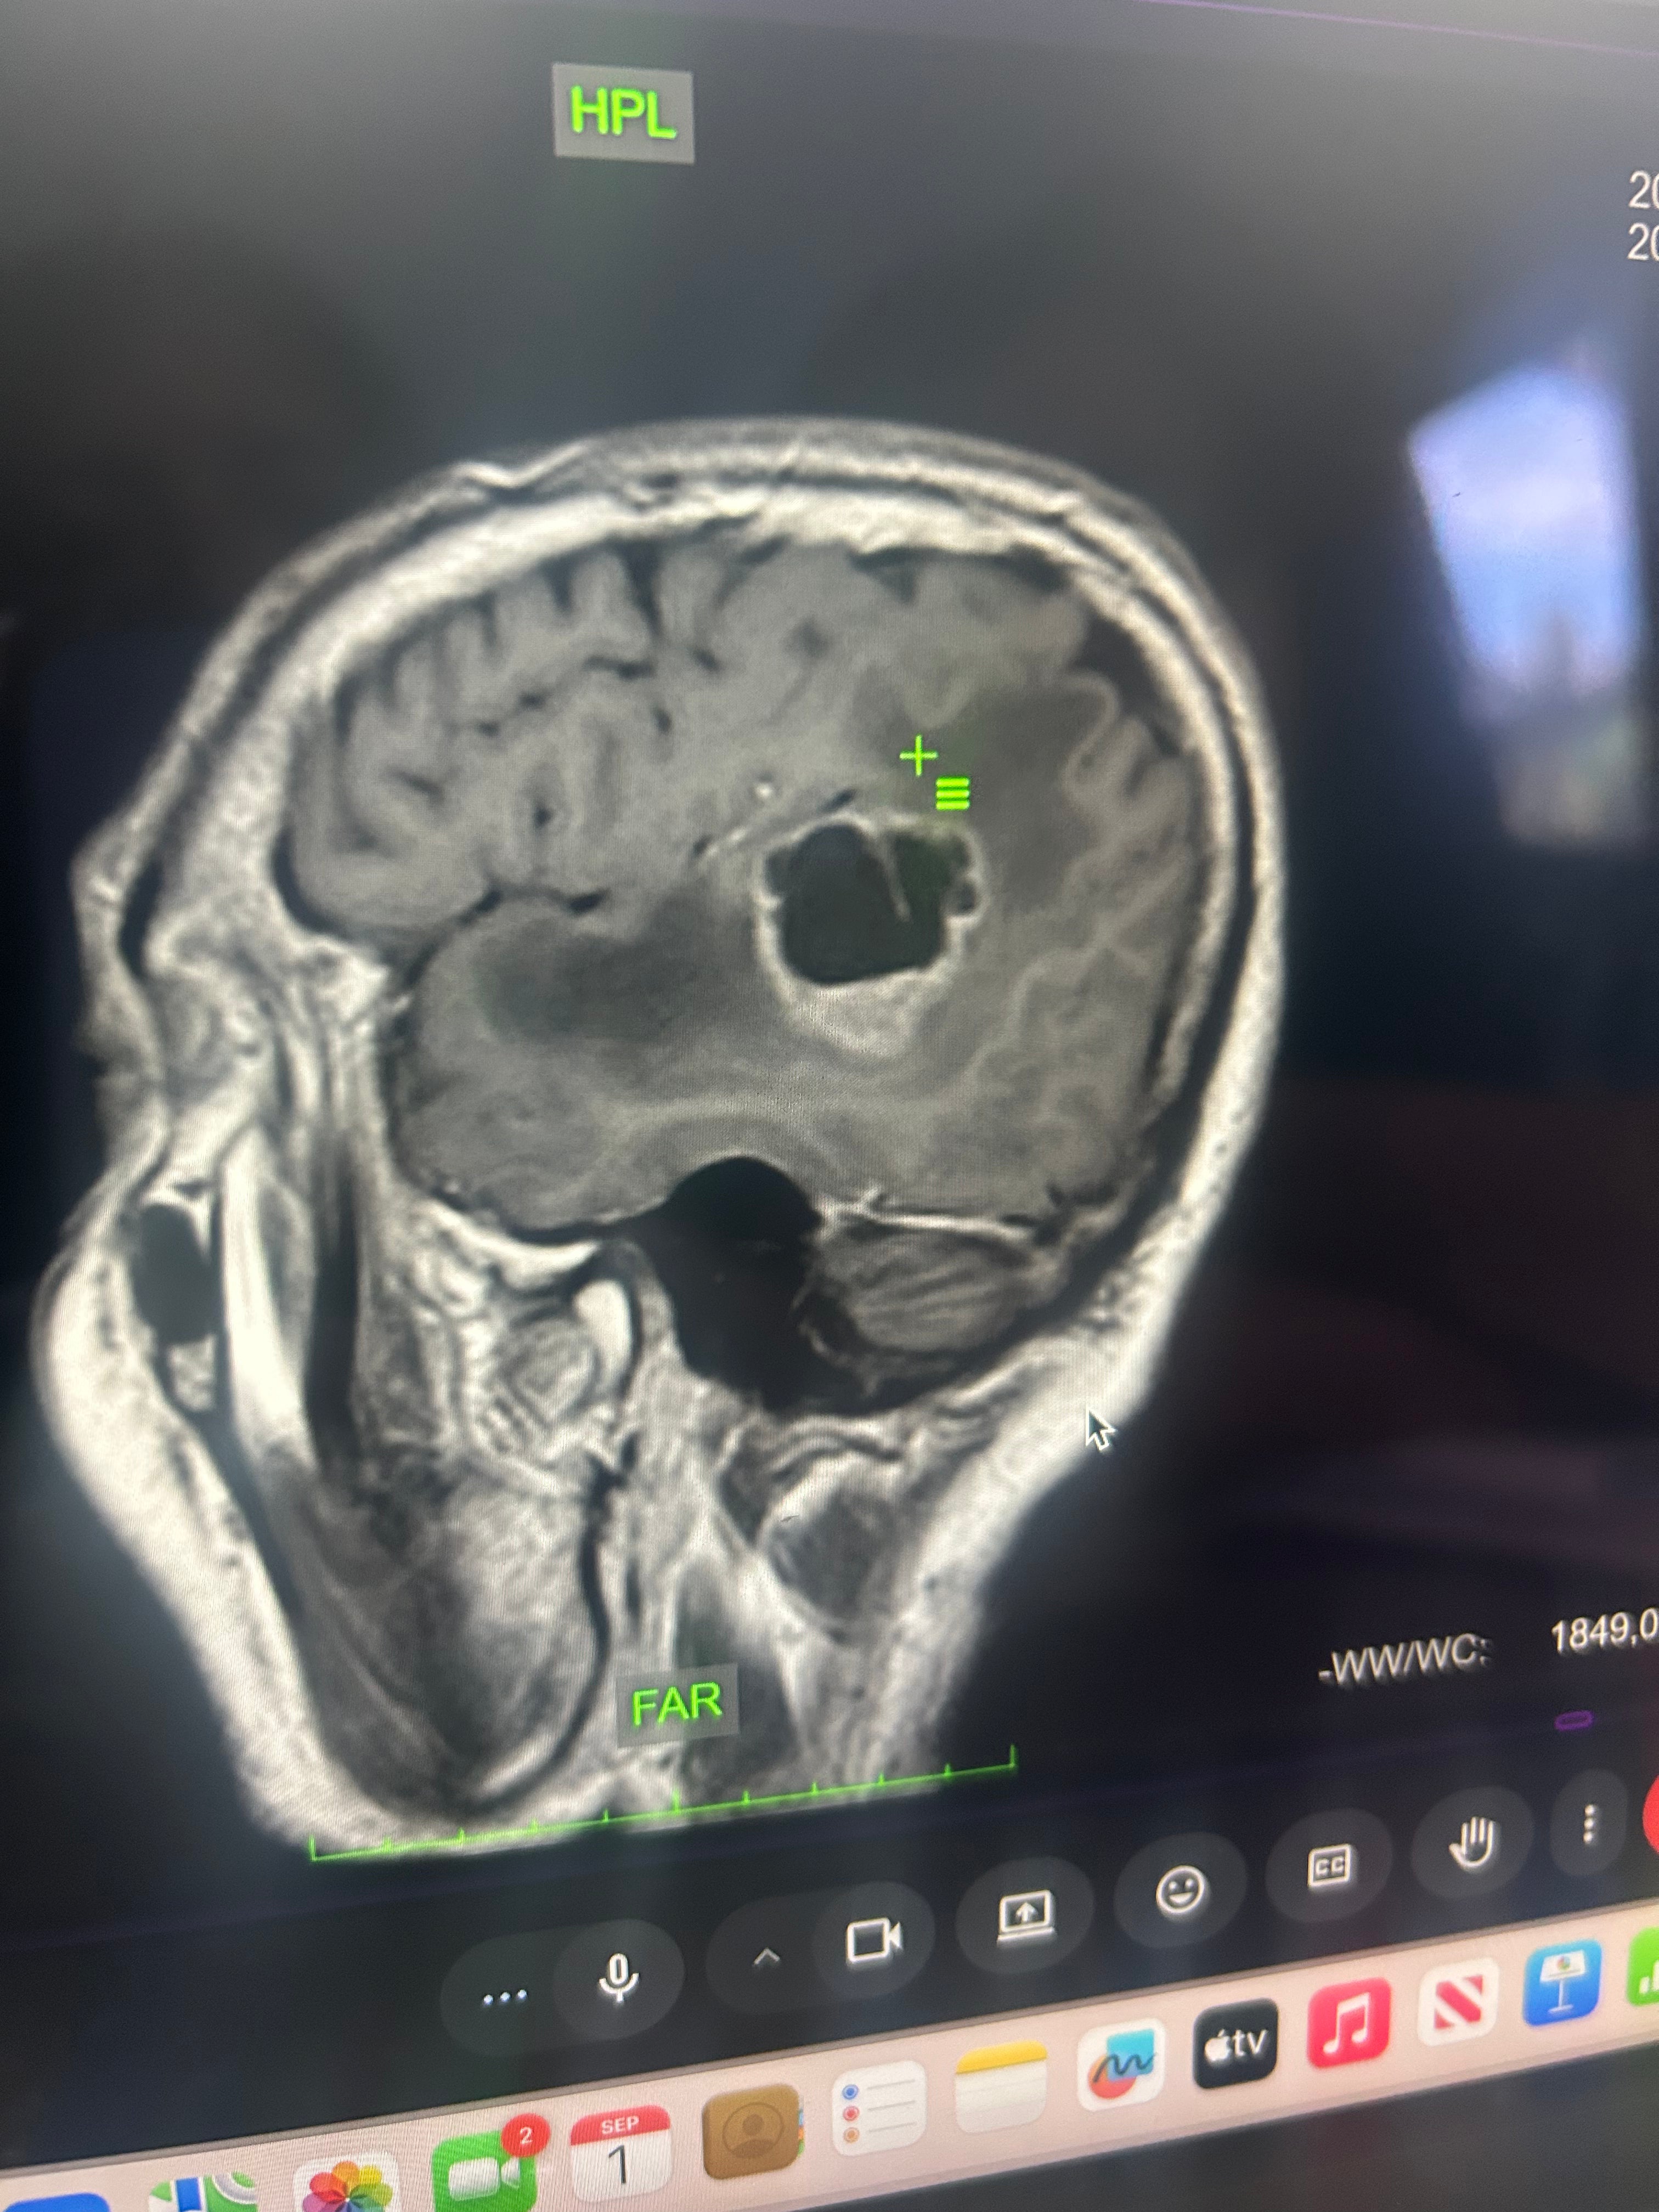

Brain Scan - Scan showing the brain tumor. The small line going through it shows the tumor is growing into two.

My dad had to leave the country in May and 3 months later he has yet to start any treatment.Due to Colombia's healthcare system, that means months of waiting for each test with insurance.While he waited, the cancer spread to his kidney. Now to his brain. Two tumors are causing him to loose feeling from the left side of his face, his mouth, and his eye. He is at risk for paralysis.

He has been hospitalized multiple times, coughing blood, in excruciating pain, all while being thousands of miles away from us. Right now my dad urgently needs radiation, chemotherapy, medications, and housing close to the hospital so he can get treatment safely.